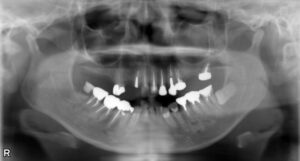

上顎8本欠損症例

BEFORE AFTER 56歳女性/下顎4本欠損/インプラント埋込手術 【治療内容】 神経の処置をしていた歯の状態が悪…